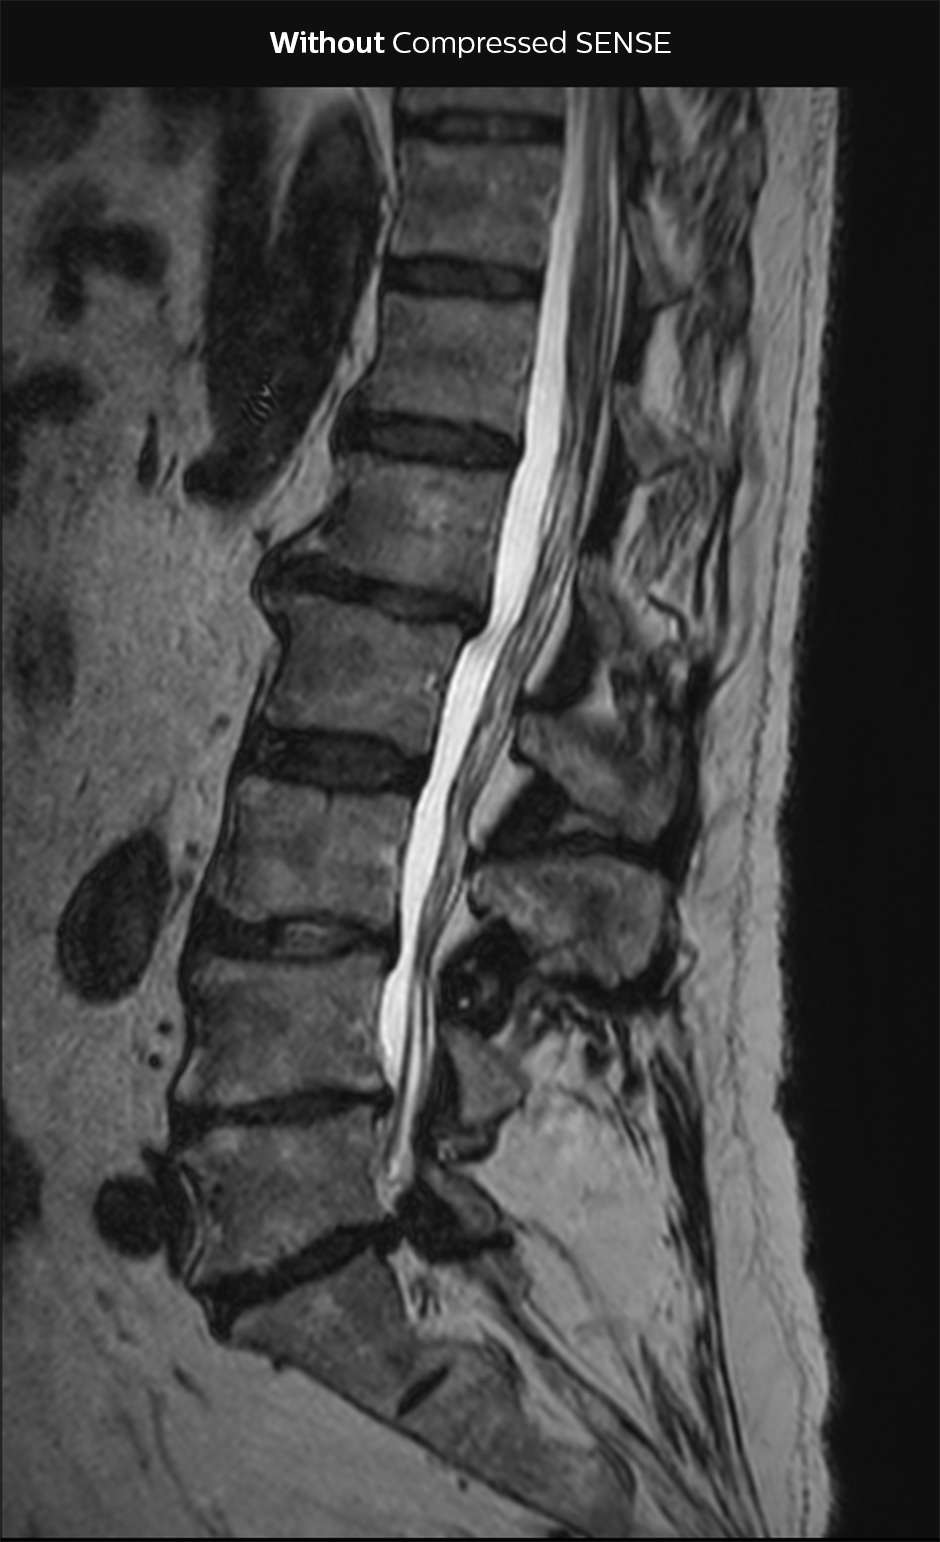

Accelerating lumbar spine

In this example Compressed SENSE has a 26% shorter scan time and improved spatial resolution simultaneously.

3D T2 SpineVIEW lumbar spine WITHOUT Compressed SENSE

3D T2 SpineVIEW, scan time 6:29 min, voxel size 1 x 1 x 1.4 mm

3D T2 SpineVIEW lumbar spine Compressed SENSE factor7

3D T2 SpineVIEW, scan time: 4:46 min, voxel size 0.8 x 0.8 x 1 mm